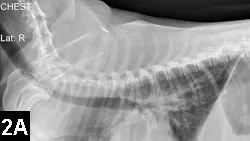

Radiography and abdominal ultrasonography

• Survey radiography is indicated for pulmonary, pleural, or abdominal hemorrhage (Figures 2A and B).

Figure 2A. Lateral thoracic radiograph of a Welsh corgi (9 years of age) following ingestion of an anticoagulant rodenticide at least 3 days before presentation. Note the mixed pattern of alveolar infiltrates and scant pleural effusion (hemorrhage).

Figure 2B. VD radiograph of the patient. Alveolar pattern in the right cranial and middle lung lobes represents one of the radiographic manifestations of pulmonary hemorrhage.